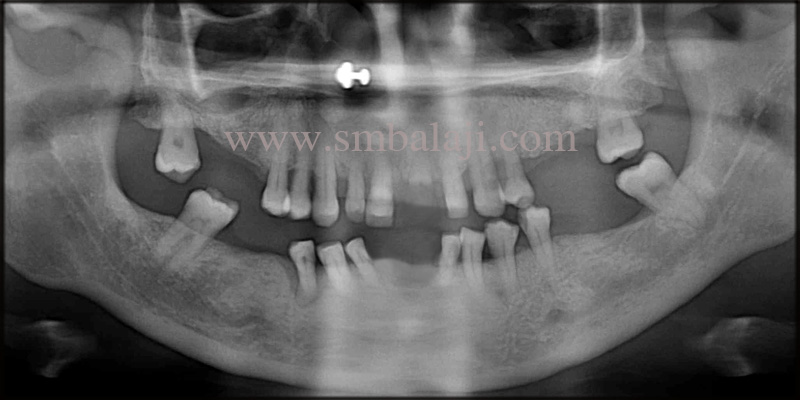

Full mouth X-ray (OPG) taken shows apicoectomy done to the root canal treated teeth in the lower anteriors. Infection around the implant and the teeth was evident.

This is a case of a 28 year old woman with a complaint of shaking lower front teeth, which induces pain and discomfort on chewing food. She stated that lately the saliva from the involved site is starting to taste salty. She gives a dental history of root canal treatment done to the lower anteriors 2 years back. After which an apicoectomy of the teeth was done a year back elsewhere, due to long standing cystic lesion at the root end of the teeth.

Subsequently, one of her lower anterior tooth started shaking, which was then extracted and replaced with a dental implant 6 months back. Over the time there was an increase in the mobility of the adjacent teeth and the dental implant. Worried with her oral condition, she approached us seeking for a solution,that could restore her well-being.